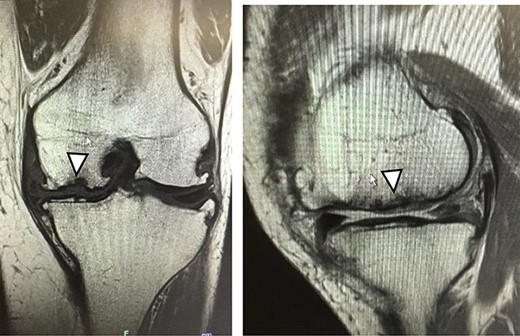

There were cartilage defects (arrowhead) in the medial femoral condyle and trochlea of the left knee (a, b).

Articular cartilage injury was shown in the medial femoral condyle (arrowhead) (2.5 × 3.5 cm; Outerbridge classification, Grade III) and trochlea (arrowhead) (1.3 × 1.7 cm; Outerbridge classification, Grade III) (a, b).

A 42-year-old female (BMI, 27.4 kg/m2) presented with 2 years of left knee medial joint pain. Active range of motion (ROM) in the left knee was from 0 to 140 degrees with no extension lag. Preoperative Tegner scores, Lysholm scores and Knee Injury and Osteoarthritis Outcome (KOOS) scores are shown in Table 1. Preoperative radiographs of the left knee joint showed mild medial osteoarthritis (OA) of the knee and hip–knee–ankle (HKA) angle of 1.5-degree varus. 1.5-Tesla MRI was performed on unit (Toshiba, Kawasaki, Japan) was used with an extremity surface coil. Proton density images were obtained using the fast spin-echo technique. A modified magnetic resonance observation of cartilage repair tissue (MOCART) system was used for the quantitative evaluation of MRI findings of the cartilage injury [15–17]. MRI showed cartilage injury of the medial femoral condyle (MFC) and trochlea of the left knee (Fig. 1).

MRI showed cartilage injury of the medial femoral condyle (arrowhead).